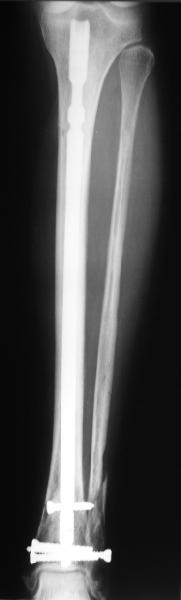

A typical case is attached, also an image with intra-op reduction obtained by a small wire distractor, in the moment of insertion a Poller wire in AP direction. Fixation by a SIGN nail. Despite the fibula was not fixed healing was obtained with the unchanged alignment.

At least both the ankle mortise and tibial alignment look acceptable, don't they?

I am just trying to illustrate that prevention of 1)tibial valgus and 2)loss of reduction can be provided without fibular plating. Small changes of conventional nailing techniques allow to maintain reduction of the tibia reliably without adjunctive fibular stabilization.